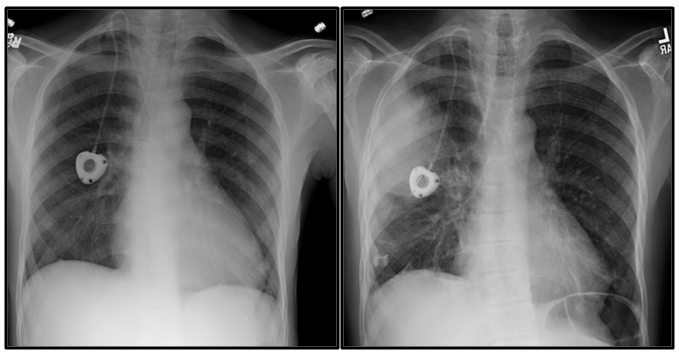

We present the case of a forty-two-year-old male with hemoglobin SS (HbSS) disease and history of fever. Additional past medical history includes hypertension (HTN), severe malnutrition, chronic leg ulcers, bilateral avascular necrosis (AVN) of femoral and humeral heads, cholelithiasis and Port-a-Cath central venous catheter placement two years prior for frequent venous access needs. Medications include hydroxyurea, oxycodone-acetaminophen and hydromorphone. Patient initially presented to the ED with one-day history of headache, generalized myalgias and reported fever of 38.9°C. Despite known SCD complications, he had been well managed for the preceding two years (one ED visit, no transfusions). Vitals on initial presentation were unremarkable (Table 1). Complete blood count (CBC) and comprehensive metabolic panel (CMP) were obtained, notable for baseline hemoglobin (Hgb) of 9gm/dL, white blood cell count (WBC) 13.2K/uL and grossly unremarkable CMP (Table 2). He received intravenous fluids (IVF) and analgesics and was discharged home after pain resolution. He returned the following day with worsening fever (40.6°C at home), headache, abdominal pain and diffuse weakness. He was afebrile upon presentation and other vitals were unremarkable (Table 1). Due to persistent headache, a lumbar puncture (LP) was performed, which showed no evidence of infection (WBC 0/uL, glucose 65mg/dL, protein 29mg/dL). Patient received IVF, analgesia, anti-emetics and was discharged home with resolution of complaints. He returned to the ED two days later, describing persistent and worsening headache, fevers, two days of emesis, and a new cough. He was afebrile but mildly hypotensive and tachycardic (Table 1). Labs and chest radiograph (CXR) were obtained (Table 2 & Figure 1). Hgb 7.7gm/dL, bilirubin 14mg/dL and lactate 2.38mmol/L. Blood and urine cultures were ordered, although never drawn. CXR revealed a large right middle lung zone infiltrate (Figure 1). He received 2L normal saline (NS) bolus, empiric levofloxacin and was admitted to the inpatient ward.

Figure 1 Chest Radiographs

Patient became increasingly confused, tachycardic and hypotensive despite fluid resuscitation, and transferred to the intensive care unit (ICU). STAT head, chest and abdominal CT scans were acquired and antibiotics were broadened. Chest CT showed multilobar right-sided airspace disease. Patient was intubated for worsening respiratory status despite BiPAP and transferred to the regional referral center for exchange transfusion and further management of acute chest syndrome (ACS). A bronchoalveolar lavage (BAL) for culture and sensitivities was obtained at the time of intubation. He received one unit of packed red blood cells (pRBCs) during transport. In the ICU, repeat laboratories returned suggestive of acute MOF (Table 2). He received an exchange transfusion and an additional 3 units of pRBCs for persistent anemia (Hgb 7.7gm/dL, reticulocyte count 1.6%), required norepinephrine and vasopressin drips for hypotension, developed acute renal insufficiency (creatinine 1.75mg/dL, baseline 0.7mg/dL), stress-induced cardiomyopathy (ejection fraction 21%), and persistent respiratory failure requiring ventilator support until hospital Day #10. His respiratory culture grew Streptococcus pyogenes on hospital Day #2. Antibiotics were narrowed to ceftriaxone to complete a 14-day course. Blood and urine cultures throughout showed no growth, although drawn after the initiation of antibiotics. Despite aggressive management in the ICU the patient’s course was complicated by development of an exudative right-sided pleural effusion requiring tube thoracostomy on hospital day #2, large venous thrombus extending from left external iliac to left common iliac vein on hospital day #8 requiring therapeutic anticoagulation, dry-gangrene of bilateral toes (hospital day #15) requiring bilateral trans metatarsal amputations and hematochezia with cytomegalovirus colitis and rectal ulcer (hospital day # 29) requiring treatment with valgancyclovir. He required consultation from pulmonary critical care, gastroenterology, hematology, infectious disease, vascular surgery and rehabilitation during his hospital course. On hospital day #37, patient was discharged home.